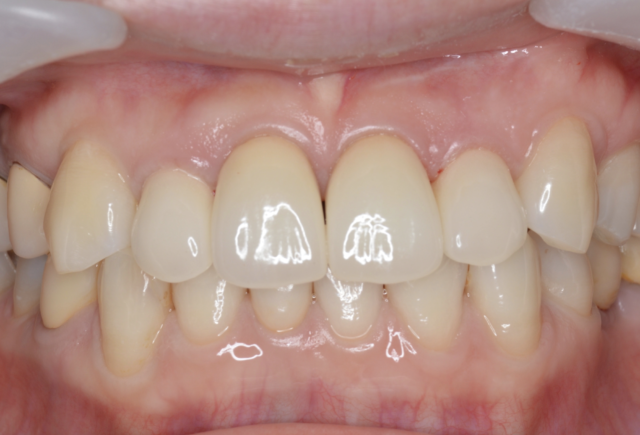

AFTER

右上2と左上2の歯肉形態を修正し、上顎2~2を補綴することで、審美性を獲得した。

右下1は右下2と左下1の形態を少し修正して補綴している。

術後

5年以上経過